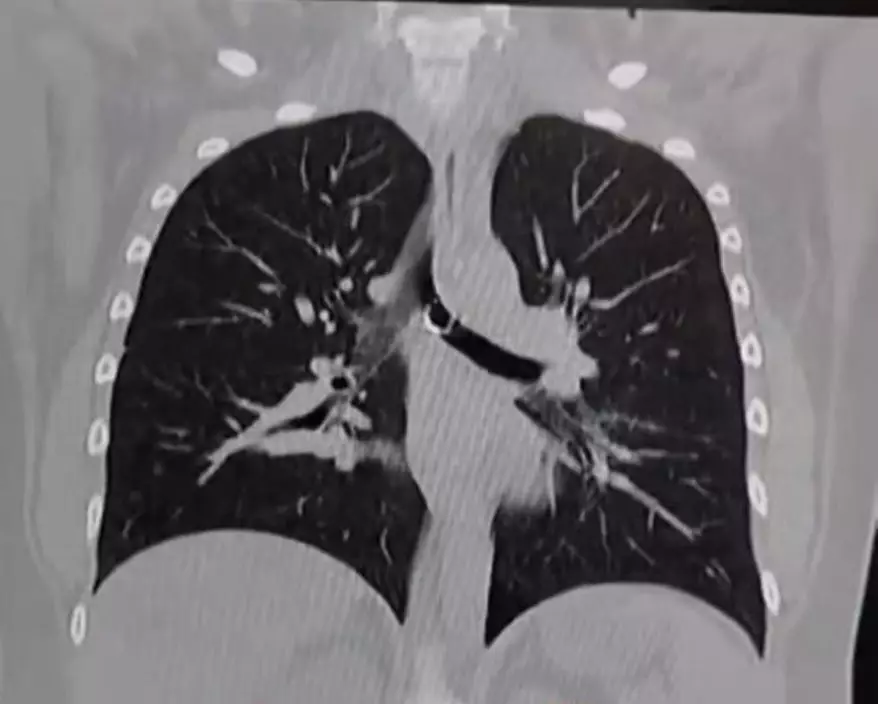

綜合外媒報導,墨西哥一名26歲女子巴拉哈斯(Monica Deyanira Cabrera Barajas)早前因持續咳嗽逾1個月未見好轉,遂前往醫院檢查。原以為只是普通小病,結果經X光檢查後發現,她的鼻環竟卡入肺部位置,甚至距離主動脈僅約0.5毫米,險些造成致命後果。

鼻環緊貼主動脈 誤吸入肺部恐致嚴重併發症

醫生透過影像檢查發現,巴拉哈斯的肺部內竟有一枚金屬鼻環,且緊貼主動脈,若位置稍有變動,隨時可能刺穿肺部或血管,引發氣胸或大量出血死亡。巴拉哈斯事後於TikTok分享自身經歷表示,起初並未察覺鼻環遺失,更未想到會被「吸入體內」,推測或因睡眠期間不慎令鼻環脫落並誤吸入呼吸道,最終進入肺部。